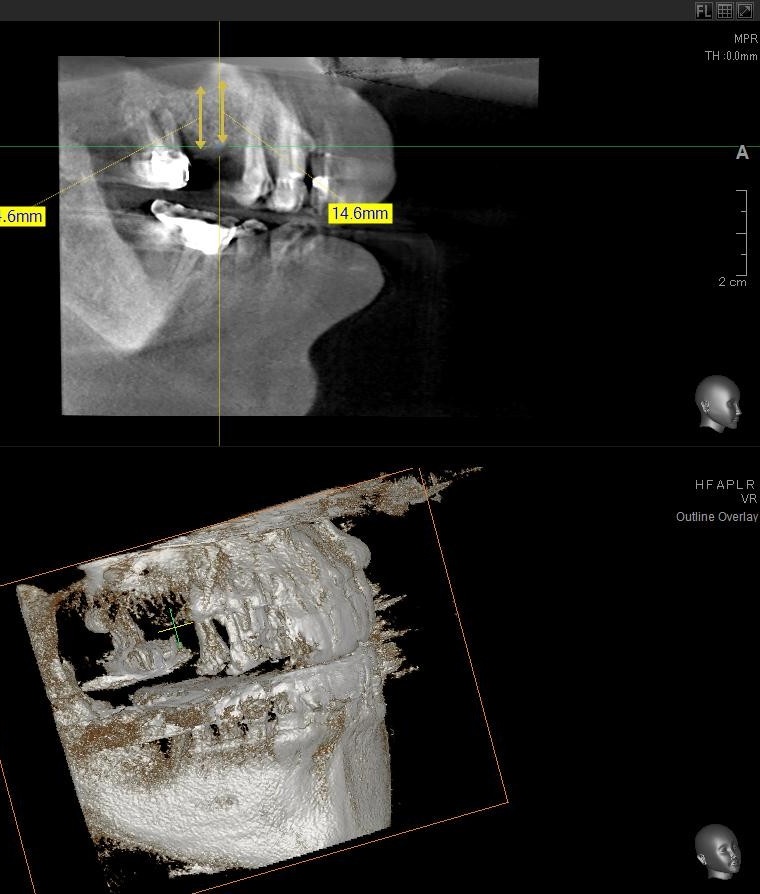

今回の患者様はインプラント植立を希望され、右上5番目・6番目の合計2本の植立が決まりました。

ドリルの先端を細い物から徐々に大きい物に変えながら、植立するインプラント体のネジの部分を除いた胴の部分の太さに合わせた大きさの穴を開けていきます。

開けた穴に、専用道具を使ってネジを締めるように長さ2センチ程のインプラントを骨に埋め込んでいきます。

続けて右上6番目も同じように植立していきます。

インプラントオペでは、複数本を植立する場合でも、当時進行はせず、1本ずつ同じ工程を繰り返して植立します。